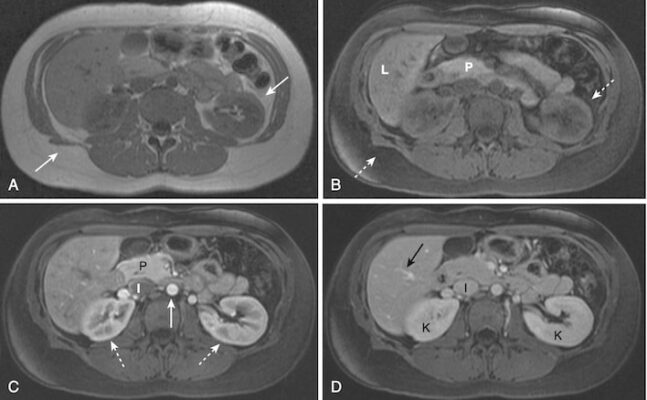

- Mỡ bình thường sáng trên hình ảnh T1w nhưng sẽ tối trên hình ảnh T1 ức chế mỡ T1 (Hình 8)(còn gọi là xoá mỡ).

- Tính năng này rất hữu ích khi cố gắng xác định các tổn thương chứa mỡ như u quái buồng trứng, u tủy mỡ thượng thận và liposarcoma (Hình 9), bởi vì chúng sẽ thay đổi từ sáng trên các hình ảnh không ức chế mỡ chuyển thành tối trên các hình ảnh ức chế mỡ.

- Ức chế mỡ cũng cần thiết để đánh giá các mô sau khi dùng thuốc đối quang từ gadolinium.

- Mỡ sáng trên T1 ngay cả khi không dùng gadolinium. Để tăng khả năng phát hiện sự tăng cường độ tương phản trong mỡ, hình ảnh trước và sau dùng đối quang từ thường được ức chế mỡ (có nghĩa là làm tối) để nâng cao tác dụng của gadolinium (Hình 10).